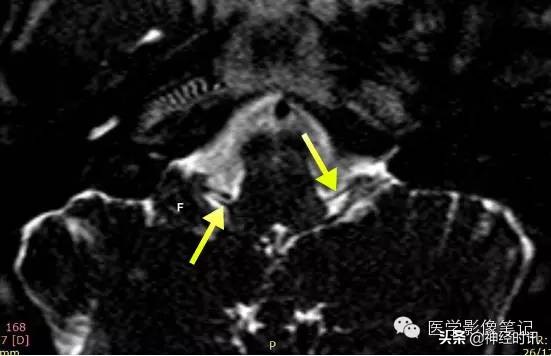

嗅神经的嗅丝

冠状位,嗅神经进入筛孔的一段